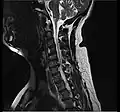

- Magnetic resonance imaging is the gold standard study for confirming a suspected LDH. With a diagnostic accuracy of 97%, it is the most sensitive study to visualize a herniated disc due to its significant ability in soft tissue visualization. MRI also has higher inter-observer reliability than other imaging modalities. It suggests disc herniation when it shows an increased T2-weighted signal at the posterior 10% of the disc. Degenerative disc diseases have shown a correlation with Modic type 1 changes. When evaluating for postoperative lumbar radiculopathies, the recommendation is that the MRI is performed with contrast unless otherwise contraindicated. MRI is more effective than CT in distinguishing inflammatory, malignant, or inflammatory etiologies of LDH. It is indicated relatively early in the course of evaluation (<8 weeks) when the patient presents with relative indications like significant pain, neurological motor deficits, and cauda equina syndrome. Diffusion tensor imaging is a type of MRI sequence used for detecting microstructural changes in the nerve root. It may be beneficial in understanding the changes that occur after herniated lumbar disc compresses a nerve root, and might help in differentiating the patients that need surgical intervention. In patients with a high suspicion of radiculopathy due to lumbar disc herniation, yet the MRI is equivocal or negative, nerve conduction studies are indicated.[44] T2-weighted images allow for clear visualization of protruded disc material in the spinal canal.

MRI scan of cervical disc herniation between C5 and C6 vertebrae -

MRI scan of cervical disc herniation between C6 and C7 vertebrae -